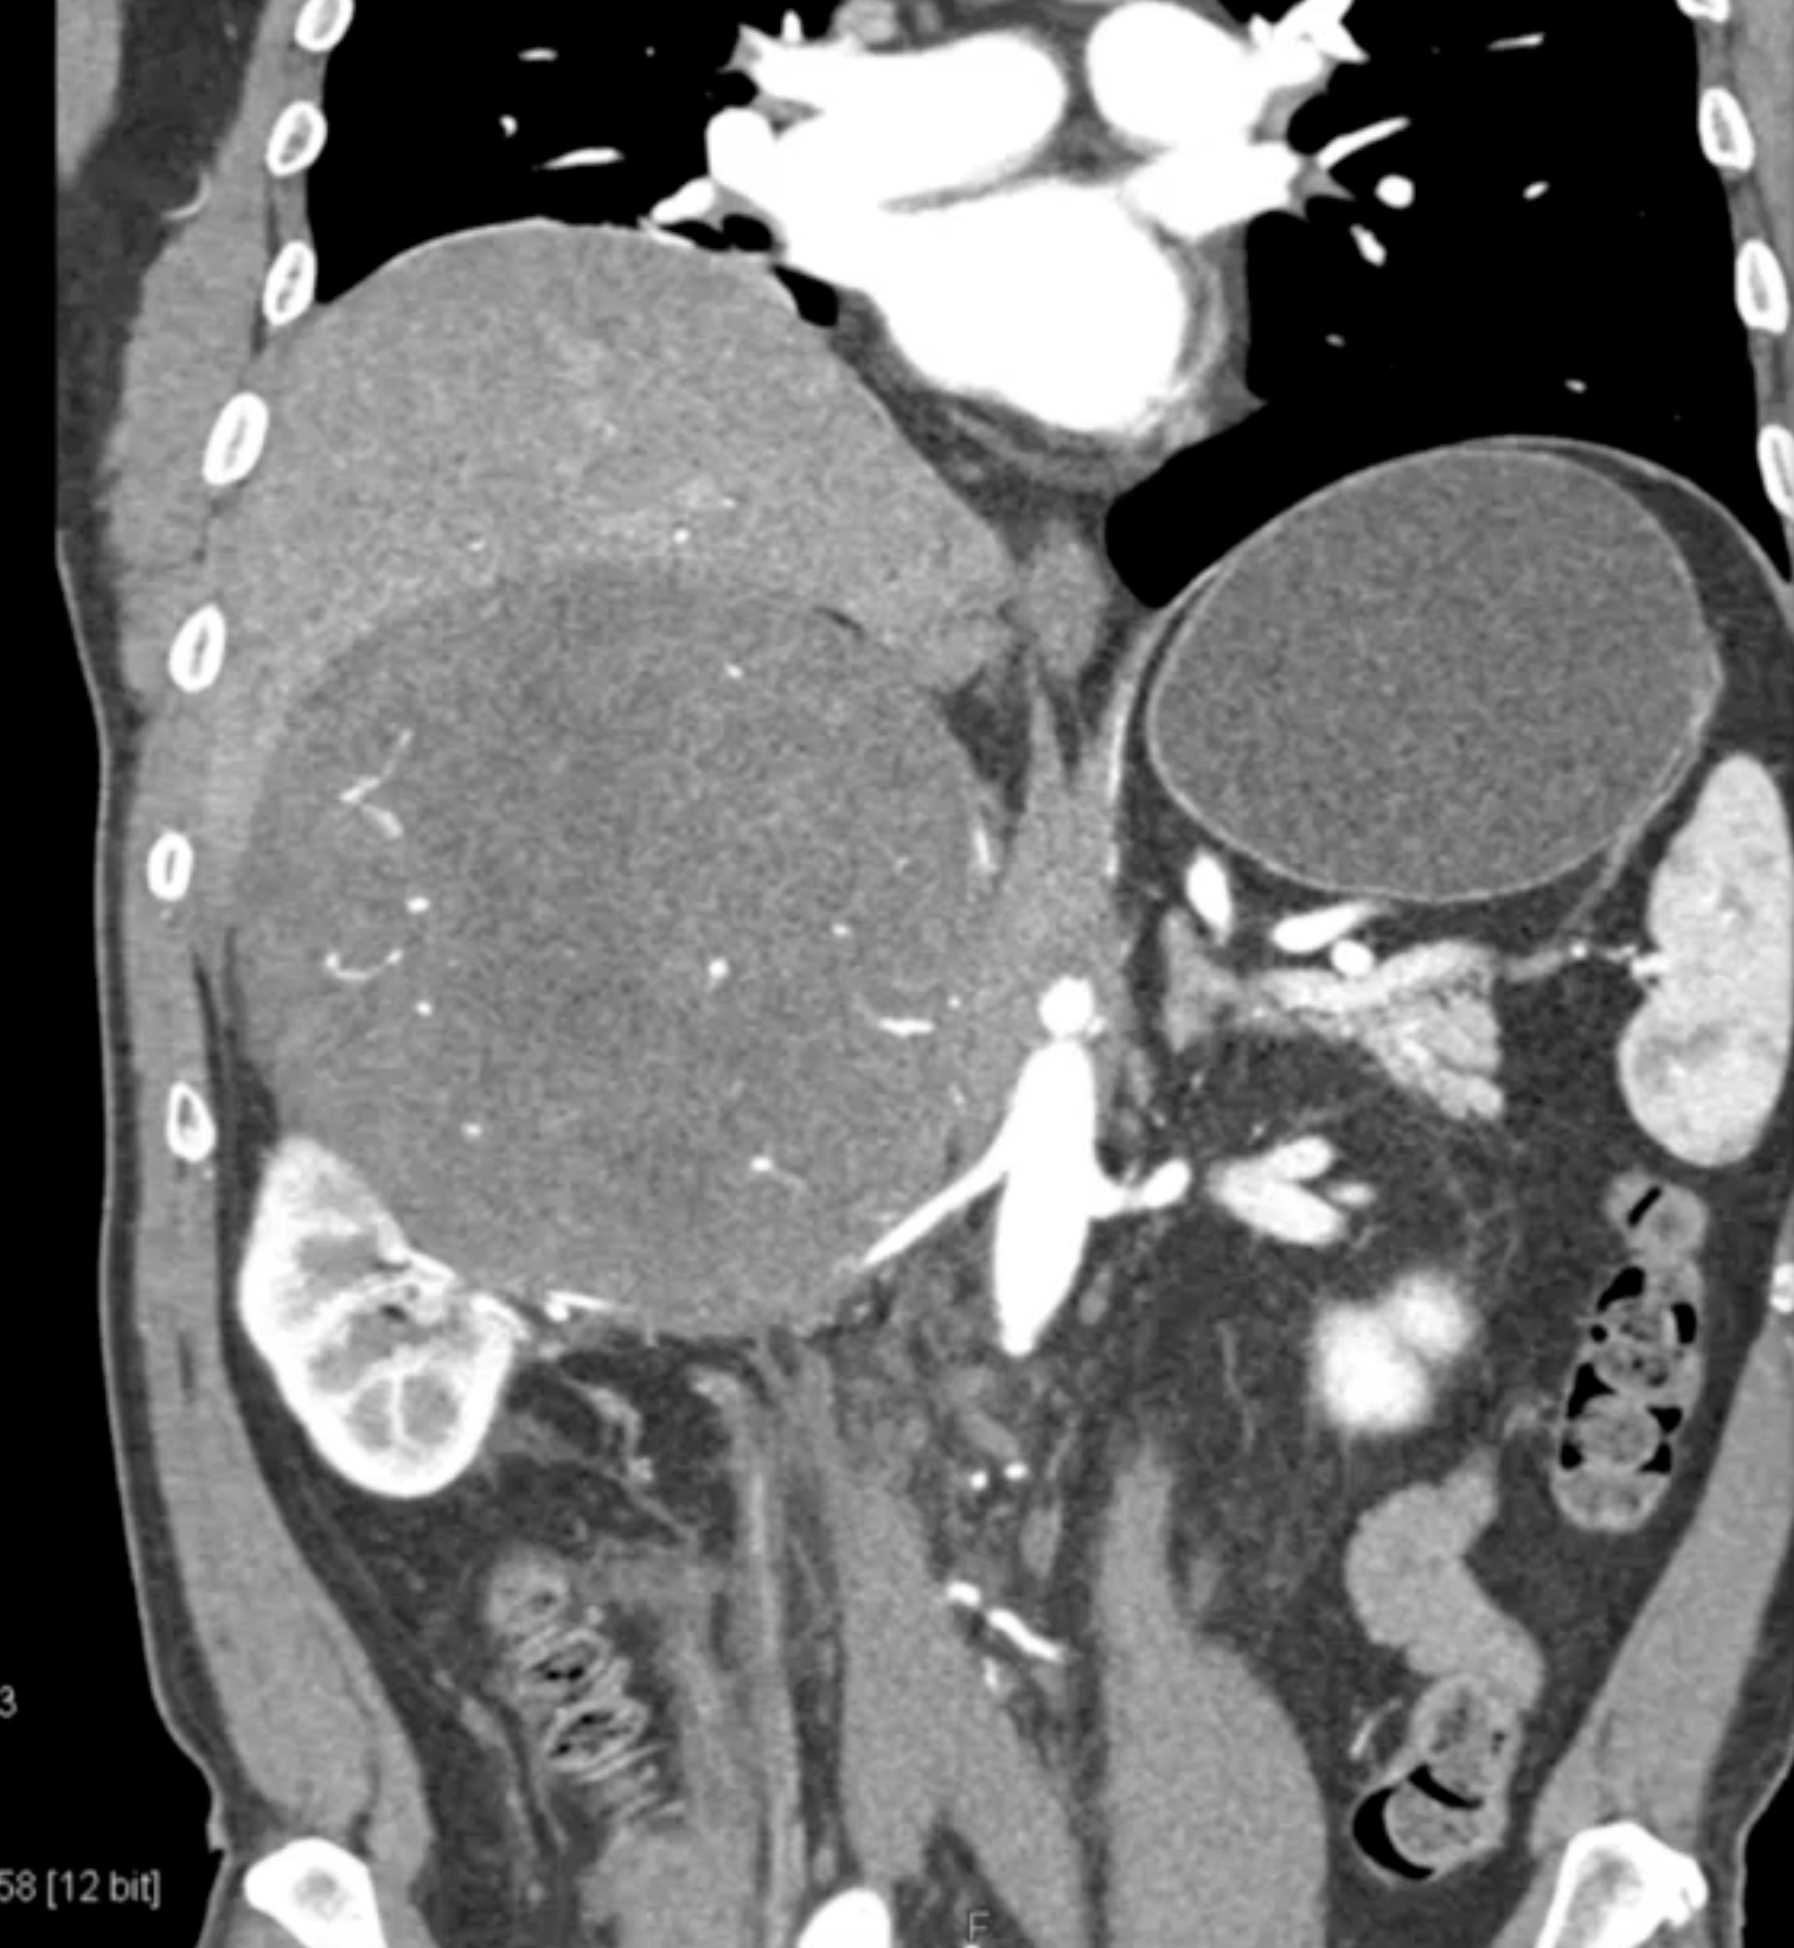

Left Adrenal Metastases from Renal Cell Carcinoma